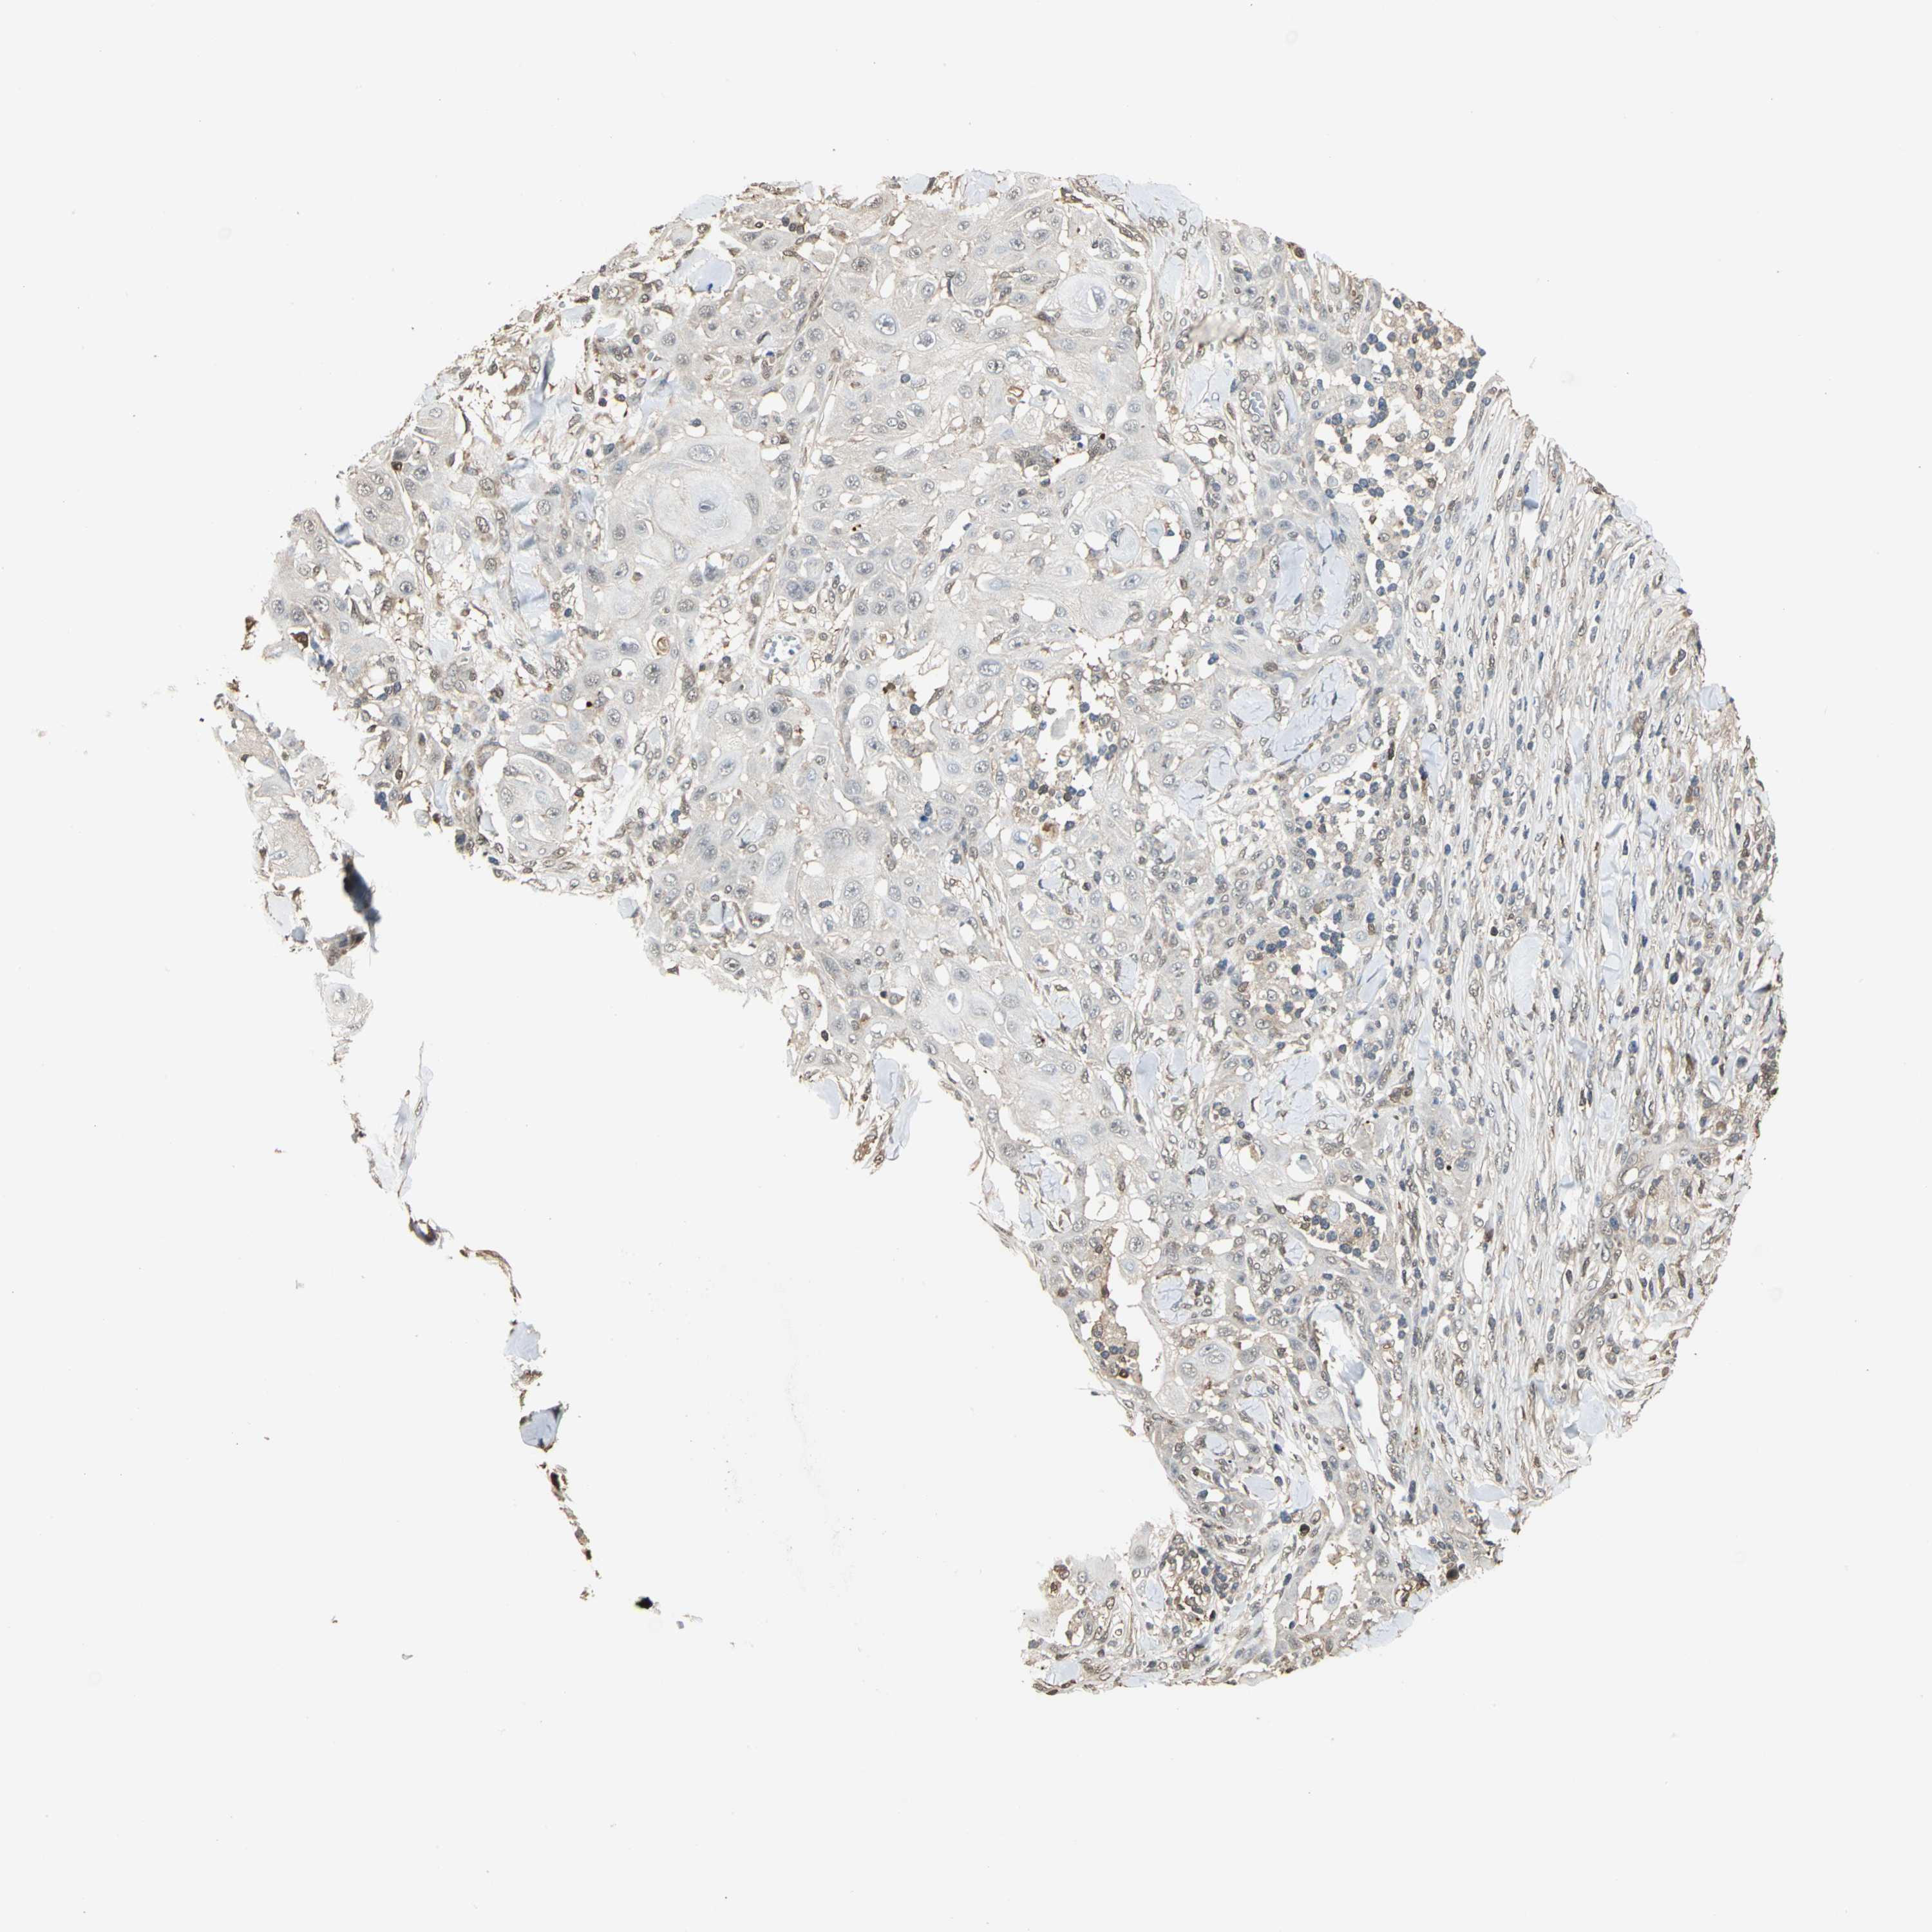

Basal cell and squamous cell cancer

SKIN CANCER - Protein expressioni

A mouse-over function shows sample information and annotation data. Click on an image to view it in a full screen mode. Samples can be filtered based on level of antibody staining by selecting one or several of the following categories: high, medium, low and not detected. The assay and annotation is described here.

Antibody stainingi

Antibody staining in the annotated cell types in the current human tissue is reported as not detected, low, medium, or high, based on conventional immunohistochemistry profiling in selected tissues. This score is based on the combination of the staining intensity and fraction of stained cells.

Each image is clickable and will lead to virtual microscopy that enables deeper exploration of all samples and also displays staining intensity scores, fraction scores and subcellular localization as well as patient and tissue information for each sample.

Antibody HPA004190

Antibody CAB005870

Squamous cell carcinoma, NOS

Basal cell carcinoma